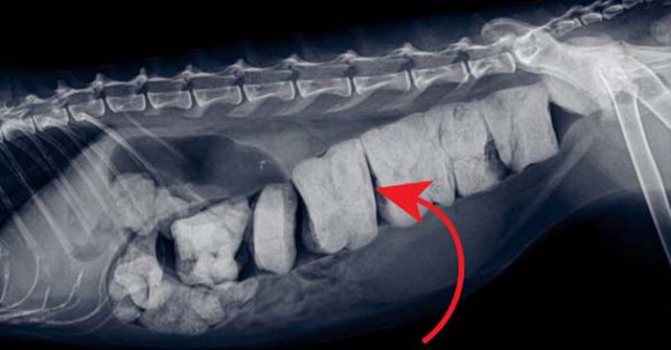

УЗИ брюшной полости, рентгенография дают возможность дифференцировать мегаколон от запора и копростаза, это важно, так как лечение у всех трех патологических состояний, различно. С помощью снимков (рентген) можно визуализировать инородные тела в просвете кишки, новообразования.